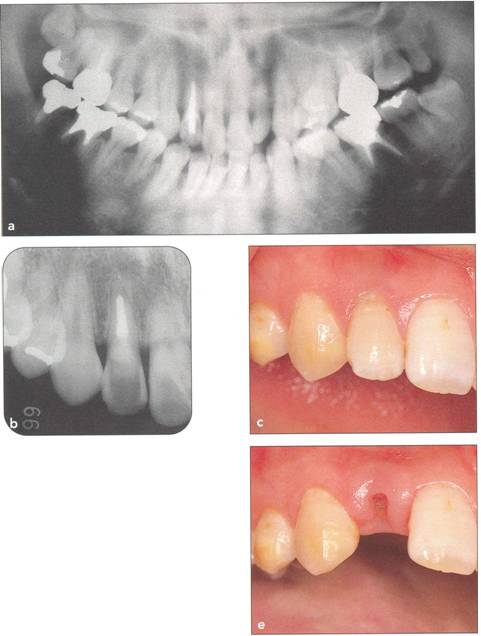

Fi 545e45f g 5-2a Panoramic view on first visit of a nineteen-year-old female patient. The maxillary right third molar will be transplanted to the area of the nonrestorable mandibular right first molar. |

Fi 545e45f gs 5-2b and 5-2c Preoperative view of the maxillary and mandibular arches. |

Fi 545e45f gs 5-2d and 5-2e Preoperative view of the tooth to be extracted. |

Fi 545e45f gs 5-2f and 5-29 Preoperative view of the donor tooth. |

Fi 545e45f g 5-2h Extracted donor tooth. This tooth seems to be at developmental stage 6. |

Fi 545e45f g 5-2i The recipient site right before transplant procedure (2 weeks after extraction of the first molar). |

Fi 545e45f g 5-2j After suturing of the gingival flap and fixation of the donor tooth using sutures. |

Fi 545e45f g 5-2k After transplantation. |

Fi 545e45f g 5-21 Two months after transplantation. |

Fi 545e45f g 5-2m Two months after transplantation. In a developing tooth, pulpal healing is expected. One must, however, carefully watch for signs of resorption or development of bony lesions indicating pulp necrosis. |

Fi 545e45f g 5-2n Eight months after transplantation. Obliteration of the pulp canal from the apex has begun, indicating pulpal vitality. |

Fi 545e45f g 5-20 Two years 5 months after trans. plantation. Total obliteration of the pulp canal has occurred, which is a normal outcome. |

Fi 545e45f gs 5-2p and 5-2q Two years 5 months after transplantation. The donor tooth is restored with composite resin. |